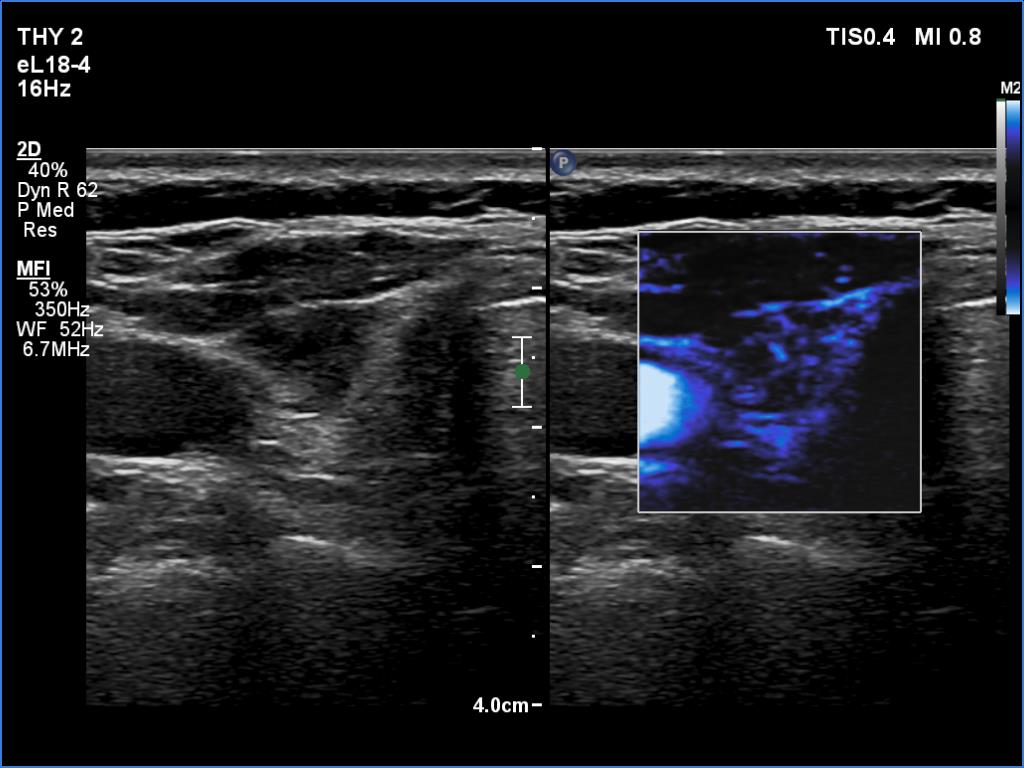

Right lobe, longitudinal scan

Right lobe, transverse view, microflow imaging. This modality disclosed vessels in regular distribution.